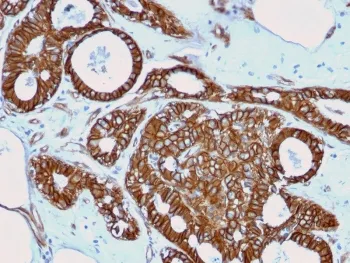

Beta Catenin Recombinant Antibody

- Applications: IF, WB, IHC-P